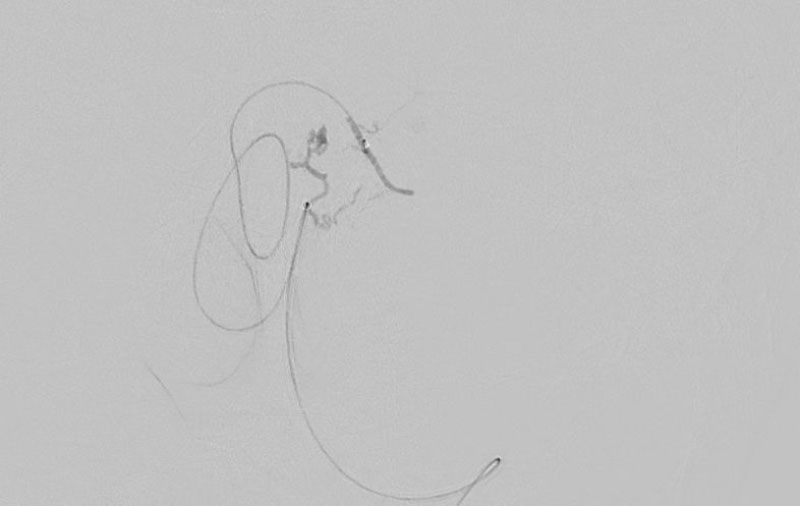

'25年11月

くも膜下出血

破裂性内頚動脈解離

40代

救急外来

No.1594 手術前

No.1594 手術中

No.1594 手術後